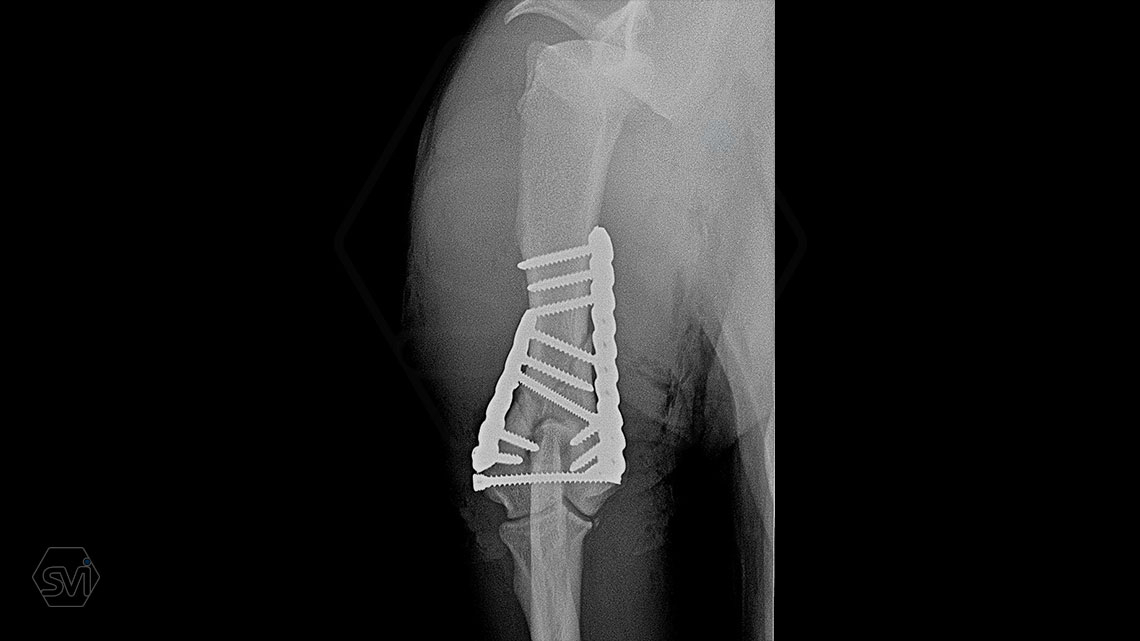

Yesterday, we operated on a Y fracture of the humerus of a 9-month-old French bulldog dog, where we used a cutable mini polyaxial straight plate (material thickness 2.0mm) and 2.4 polyaxial screws.

The fracture was favorable, the bone was not too fragmented, so we were able to plate the medial side easily, then turning the dog over, we replaced the lateral fragment as well and fixed it with a 2.4 intercondylar lag screw and with a shorter stright plate . It was very easy to work with the new plate, the surgery time was less than 2 hours. The stability is there, we placed a blind plug (screw head) in the lateral empty holes so that there is no weak point on the plate. The plate has mini polyax holes in which 2.4 and 2.0 polyax screws can be inserted (mini, 2.0-2.4 polyax system).

This plate arrangement and size is excellent for the treatment of the so common French bulldog humeral Y fractures.